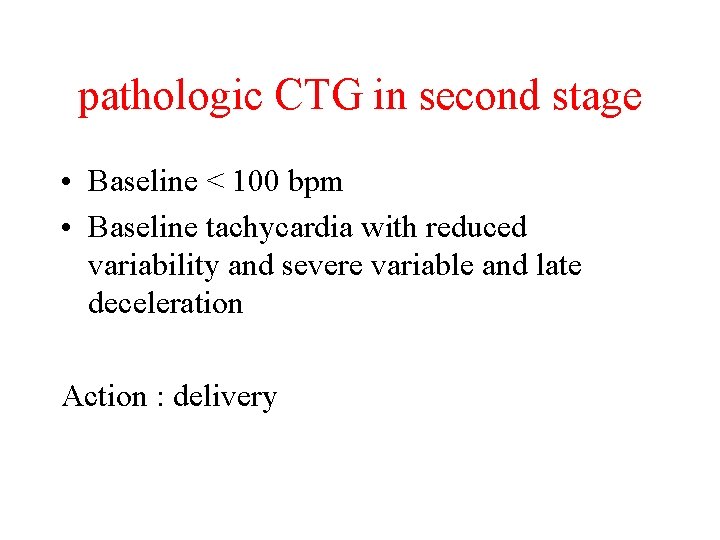

pathologic CTG in second stage • Baseline < 100 bpm • Baseline tachycardia with reduced variability and severe variable and late deceleration Action : delivery